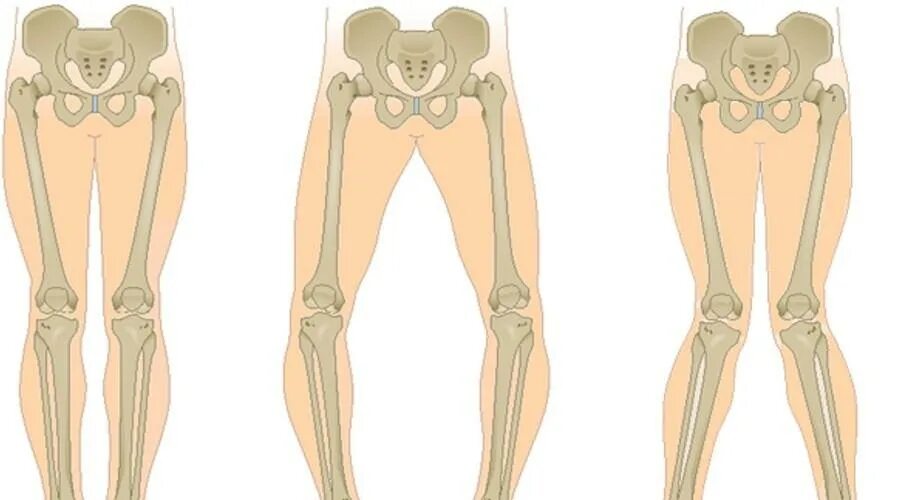

Варусная и вальгусная деформация коленного сустава. вальгус и варус коленных суставов. вальгусная и варусная деформация стопы. вальгусная и варусная деформация ног.

Варусная деформация оси нижних конечностей. х-образная деформация нижней конечности вальгусная. вальгусная и варусная деформация ног. варусная деформация коленных суставов.

Вальгусная деформация и варусная деформация. вальгусная и варусная деформация стопы. варус вальгусная деформация. варусная и вальгусная деформация коленного сустава.